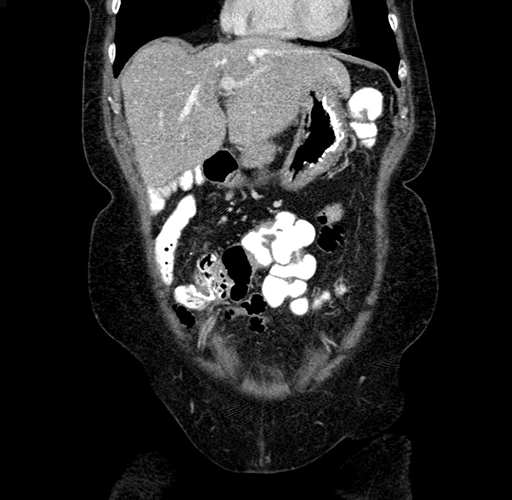

Pre-Chemo: Coronal Venous

Coronal Venous